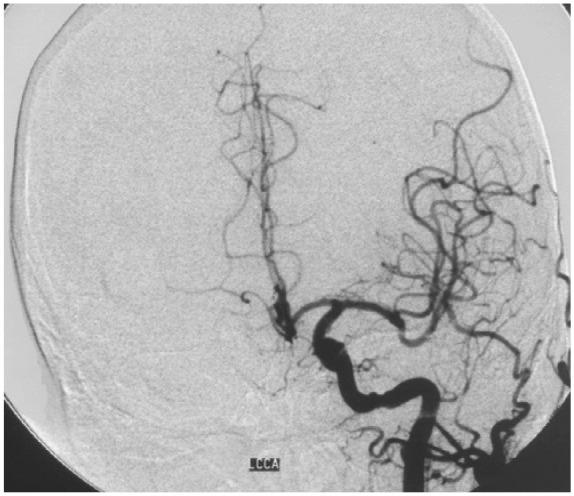

The third-generation thienopyridine prasugrel has much stronger antiplatelet effect compared to other current antiplatelet inhibitors and exhibits practically zero resistance in healthy people. Prasugrel is used as a pre- and post-treatment in percutaneous coronary or neurovascular interventions with parallel aspirin regime. However, as there is a higher reported bleeding with intraluminal interventions and meticulous technique is recommended, there is nearly non-existent international experience of open surgery under full prasugrel treatment. We present, herein, a case of open carotid endarterectomy with the eversion technique in an asymptomatic patient with carotid stenosis, who was receiving dual antiplatelet therapy with aspirin and prasugrel, due to a previous insertion of two newer drug-eluting stents at the left anterior descending artery and the right coronary artery. The resistance test to prasugrel showed complete inhibition of platelet function. Open surgery was performed under continuation of prasugrel treatment and interruption of aspirin for 3 days before surgery. No perioperative and postoperative neurologic or cardiologic event occurred. No bleeding at the cervical or cerebral area was noted.

与目前其他抗血小板抑制剂相比,第三代噻吩并吡啶类药物普拉格雷具有更强的抗血小板作用,在健康人群中几乎表现为零抵抗。普拉格雷在经皮冠状动脉或神经血管介入治疗前后使用,并与阿司匹林联合使用。然而,由于腔内介入治疗后出血的报道较多,建议采用精细技术,目前几乎没有在完全使用普拉格雷治疗下进行开放手术的国际经验。在此,我们报告一例无症状颈动脉狭窄患者,因先前在左前降支和右冠状动脉置入了两个新型药物洗脱支架,正在接受阿司匹林和普拉格雷双重抗血小板治疗,采用外翻技术进行了开放性颈动脉内膜切除术。对普拉格雷的抵抗试验显示血小板功能完全受到抑制。在继续使用普拉格雷治疗并在手术前3天停用阿司匹林的情况下进行了开放手术。围手术期和术后未发生神经或心脏事件。未发现颈部或脑部出血。